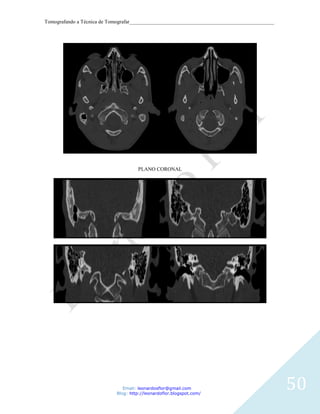

CORTES AXIAIS DA MASTOIDE

PLANO CORONAL